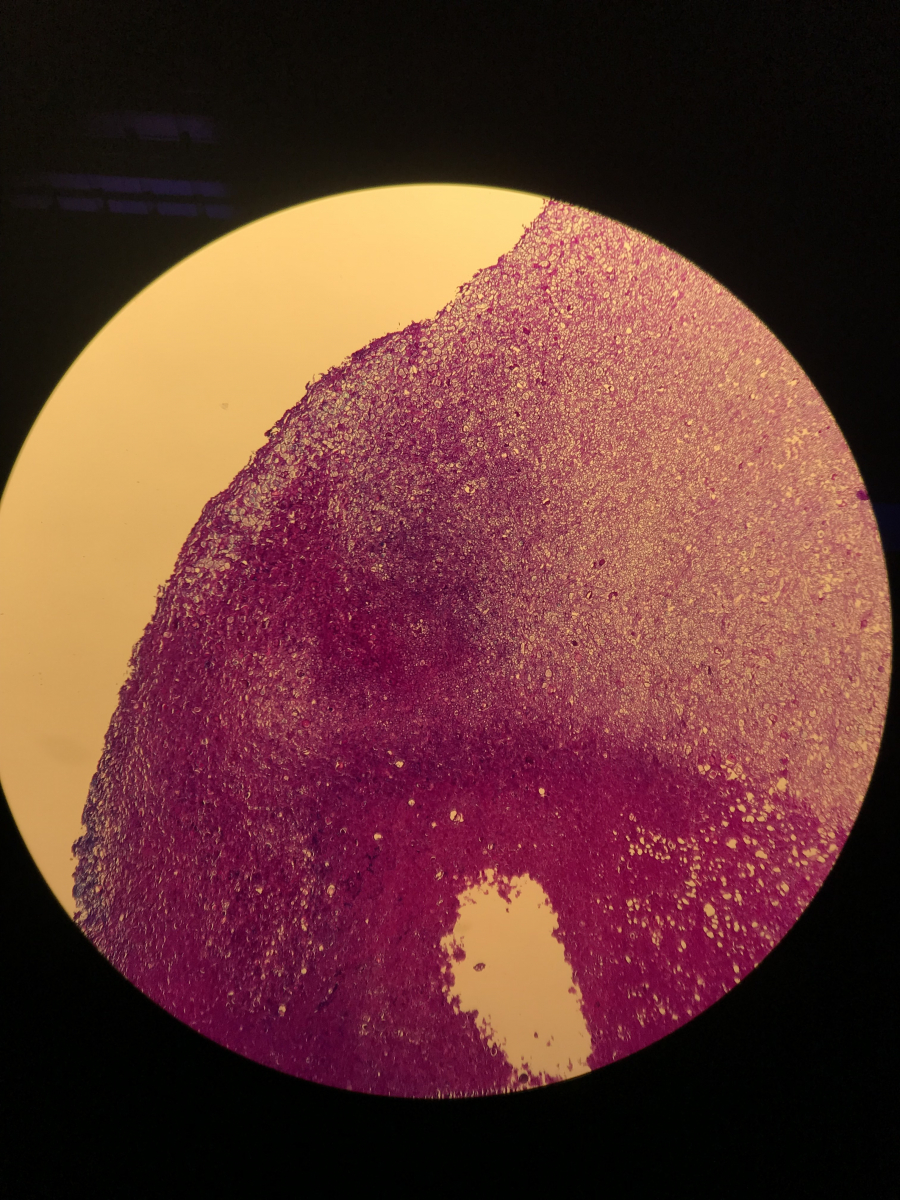

Morgen früh werde ich eine dünne Scheibe bei uns im Labor histologisch aufarbeiten… damit wir eine lichtdurchlässige Gesamtsicht erhalten ca. 1-3µm dick.